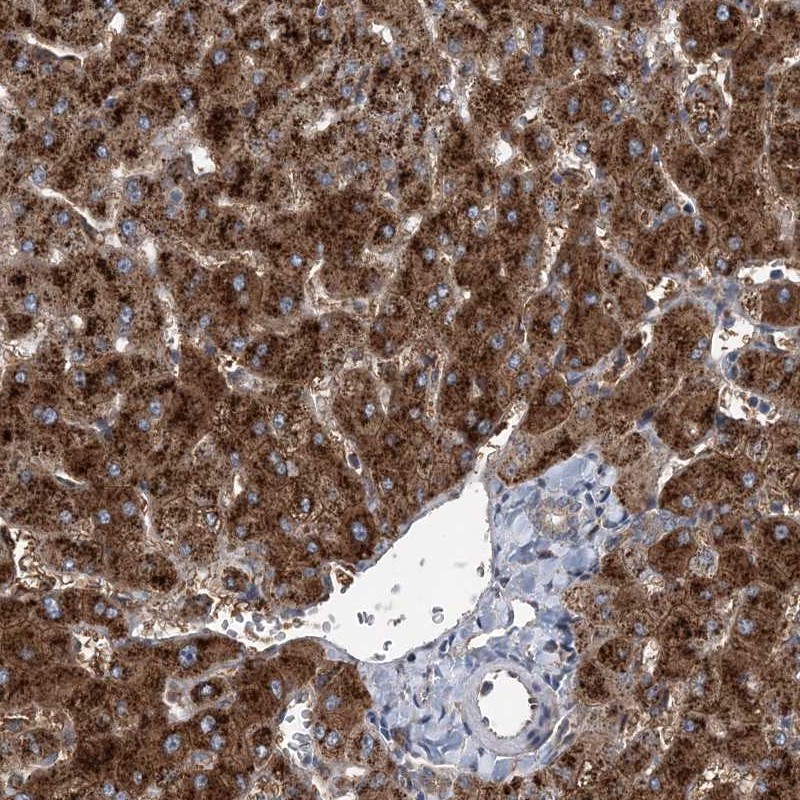

Immunohistochemical staining of human liver shows strong cytoplasmic positivity in hepatocytes.